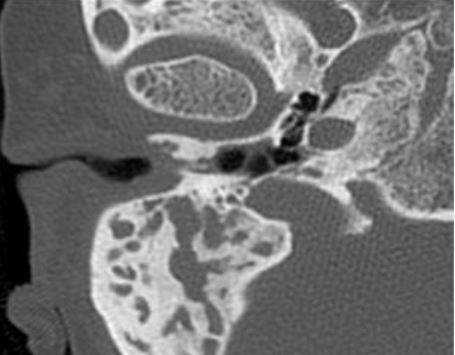

На практике у детей часто встречается вторичная холестеатома, которая развивается на фоне хронического гнойного среднего отита. Наибольшие трудности в плане дифференциальной диагностики злокачественной опухоли представляет агрессивная холестеатома у детей раннего возраста (2—5 лет). Главными отличительными ее КТ-признаками являются разрушение слуховых косточек, предсказуемый и смешанный характер деструкции, характеризующийся наличием в височной кости как участков лизиса, так и участков разрушения кости с четкими склерозированными краями [8] (рис. 5). Рисунок 5. Холестеатома аттико-антральной области. Аксиальная проекция левой височной кости. В аттико-антральной области определяется деструктивная полость (1), выполненная мягкотканным субстратом. Костные стенки полости неровные, но четкие склерозированные, слуховые косточки разрушены и не определяются.